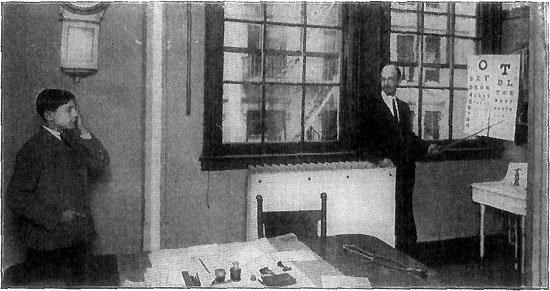

263 A School Eye-Test